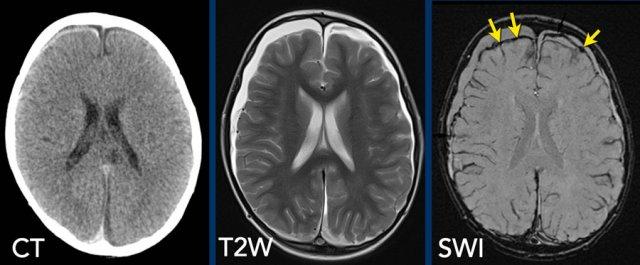

Chụp cộng hưởng từ (MRI) nhạy hơn trong việc phát hiện máu tụ dưới màng cứng.

Trong tất cả các trường hợp, chúng tôi khuyến cáo bổ sung chuỗi xung hình ảnh trọng số độ nhạy từ (SWI) vào quy trình chụp.

Hình ảnh

Máu tụ dưới màng cứng khó nhận thấy trên CT được hiển thị rõ hơn trên chuỗi xung T2W MRI, và các lắng đọng hemosiderin được thể hiện rõ ràng trên chuỗi xung SWI (mũi tên).